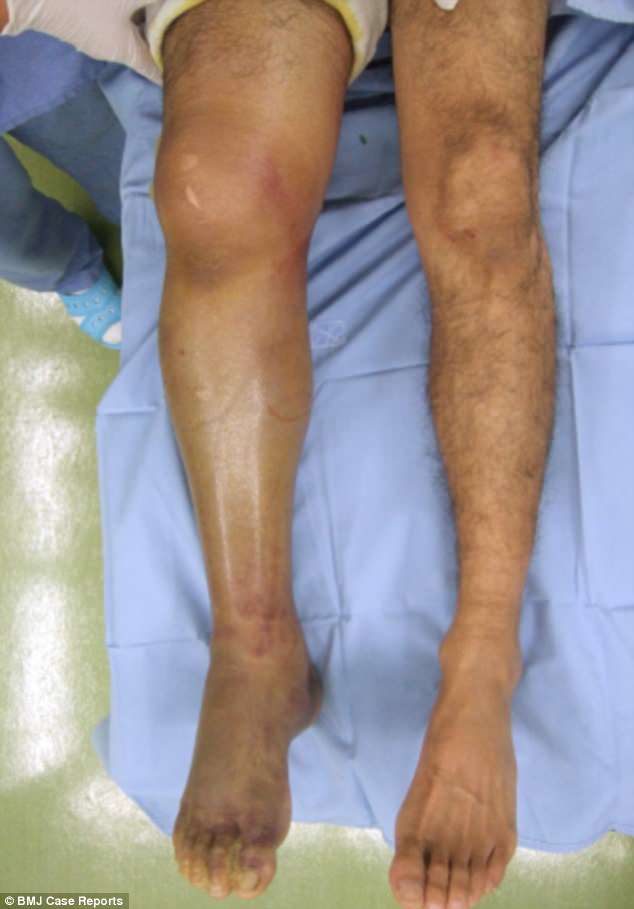

Укусы змей заставили двух мужчин бороться за свою жизнь после того, как яд заставил их мышцы опухнуть.

В 2016 и 2008 годах у двух мужчин, предположительно из Японии, был диагностирован синдром острого компартмента (ОКС) после обращения в больницу с жалобами на мучительную боль и припухлость без видимой причины.

В журнале, опубликованном в начале этого месяца, выяснилось, что у мужчин сильно увеличены мышцы, а также они страдают от повреждения почек, паралича и отмирания тканей.

После длительного пребывания в больнице, продолжавшегося до 48 дней, обоих мужчин выписали, но потребовались годы, прежде чем их перестали мучить мучительные симптомы.

Врачи считают, что их ОКС произошел из-за ядовитого укуса мамуши, самой распространенной змеи в Японии и считающейся самой опасной, убивая до 10 человек в год.

Яд мамуши вызывает разжижение тканей человека, что может вызвать сильный отек, а также потерю зрения и внутреннее свертывание крови.

Хотя ни одно из средних не показывало никаких признаков укусов, раны мамуши часто остаются незамеченными из-за того, что змеиные клыки очень тонкие и всего около 5 мм в длину, и многие считают незначительную боль осколками.

Первому пациенту потребовалась операция для снятия давления, вызванного набуханием мышц руки

У второго наблюдался заметный отек правой ноги без очевидной причины

Укус вызвал паралич, который длилось два года

В июле 2008 года 42-летний мужчина, не названный по имени, обратился в больницу с жалобами на сильную боль и опухоль в ногах.

Восемнадцатью часами ранее он споткнулся в уличной канаве, и его лечили антибиотиками в другом медицинском центре.

Там его направили к специалисту после того, как врачи заподозрили, что его мягкие ткани начали умирать из-за попадания бактерий в его тело.

В специализированной больнице ему поставили диагноз ОКС, и в течение двух часов ему сделали операцию по снятию давления на ноги.

Пациент выписан на 48-е сутки с легким параличом, который полностью не исчез в течение двух лет.